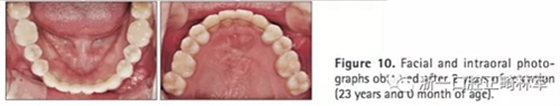

2年后隨訪提示治療結(jié)果得到保持(圖10,11,表1-3),不同階段的頭側(cè)重疊結(jié)果見圖12。